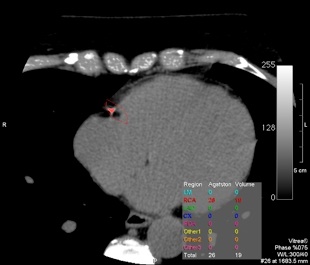

*  Calcium-Scoring